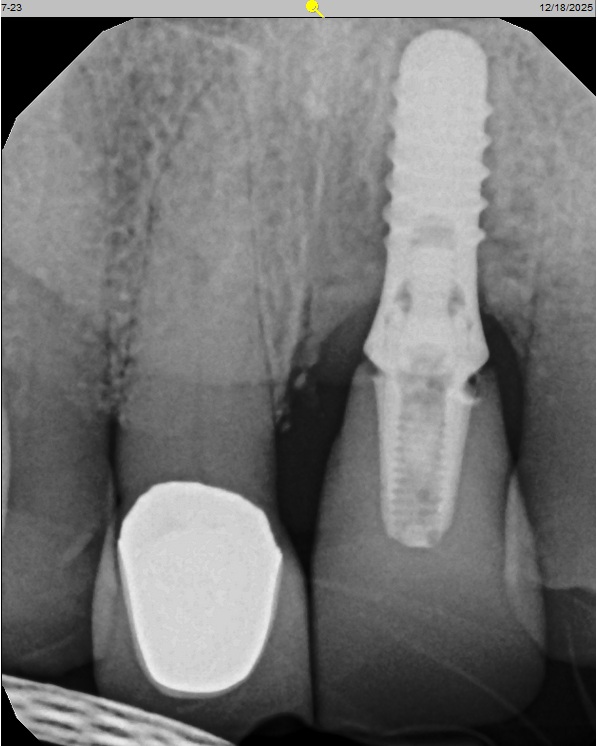

Before

After